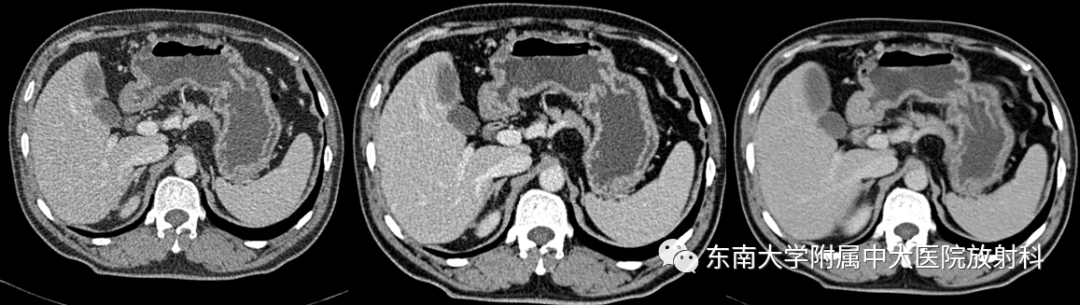

胃黏膜相关淋巴组织(MALT)淋巴瘤

病例

•男,49岁

•主诉:因“间断性腹痛、黑便4天”入院

•患者4年前无明显诱因下出现腹痛、为阵发性,夜间较重,无明显规律,解黑便数次。4年前于外院行“疣状胃炎APC术”,3年前于外院行“肠息肉内镜下粘膜切除术”;(2017-11-06)于外院行胃镜:胃体溃疡(淋巴瘤待排)